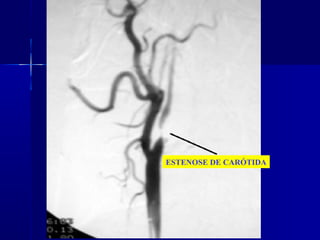

ESTENOSE DE CARÓTIDA